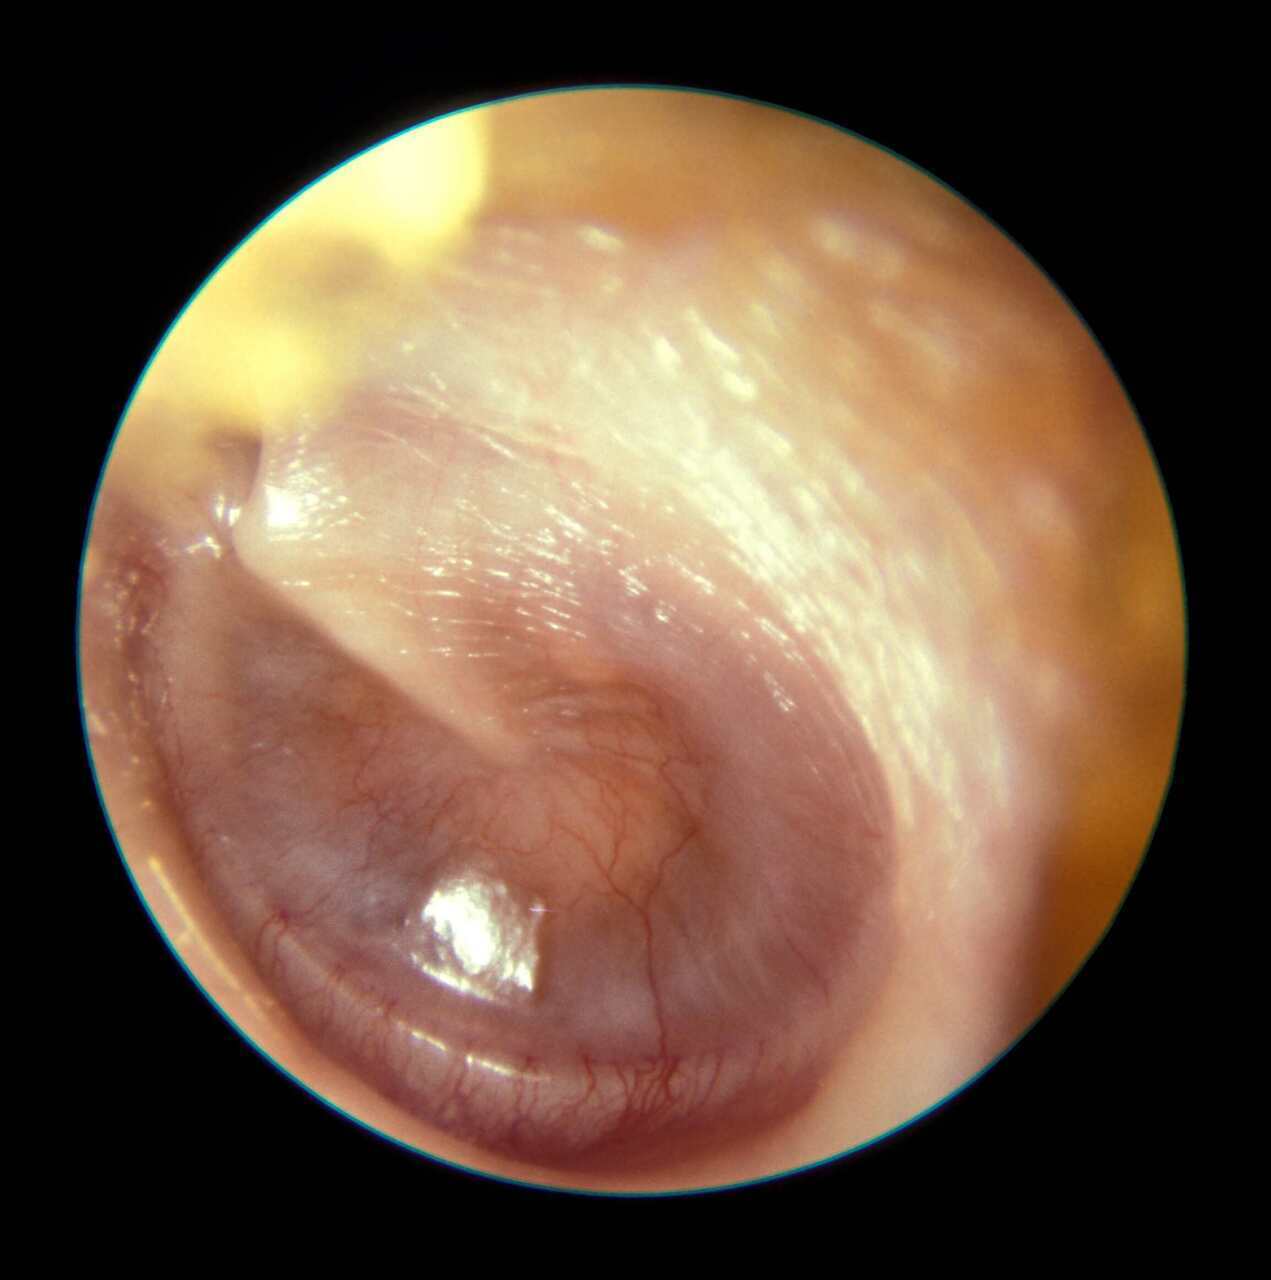

Vous examinez les tympans. Voici ce que vous constatez.

Question 1 - Que pouvez-vous dire de ce tympan (une ou plusieurs réponses exactes) ?

Il y a en effet une poche de rétraction au niveau de l’attique.

Il n’y a aucun signe local d’inflammation (rouge, aucun antécédent d’otorrhée, etc.)

Rappel sur le tympan normal : le tympan est quasiment transparent avec le marteau bien visible et bien moulé. Le triangle lumineux (reflet de la lumière) est visible dans le quadrant antéro-inférieur. Le tympan n’est pas bombant mais tendu (pars tensa), de façon radiaire à partir de l’extrémité du manche du marteau. La pars flaccida est la partie du tympan immédiatement au-dessus de l’apophyse externe du marteau.

La difficulté est parfois de distinguer une poche de rétraction d’une perforation. Ce n’est pas toujours facile et peut nécessiter un diagnostic spécialisé. Dans la plupart des cas, une perforation est bien limitée et les berges bien visibles. Dans le cas d’une poche de rétraction, le fond de caisse peut être moulé par la rétraction mais on voit généralement des reflets du tympan.

Vous constatez donc une poche de rétraction de la pars flaccida. Vous décidez de l’exploration avec un tympanogramme. Vous retrouvez le tympanogramme suivant.